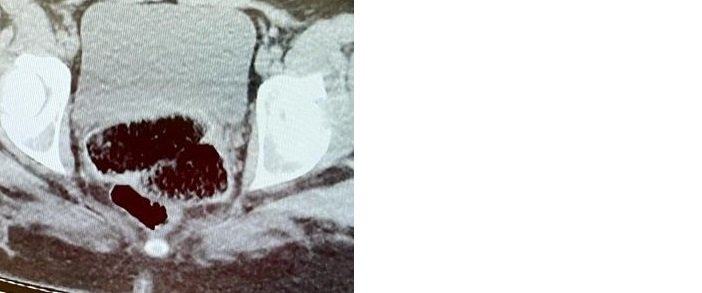

Yapılan incelemede iç genital bölge ve Anüs bölgesinde 2 parça halinde yabancı cisim tespit edildi. Yapılan tıbbı müdahaleyle yabancı cisimler çıkartıldı.

Toplamda 7 parça halinde kapsül şeklinde 534.53 gram metamfetamin maddesi ele geçirildi. Yabancı uyruklu M.K.-L.E cezaevine gönderildi.